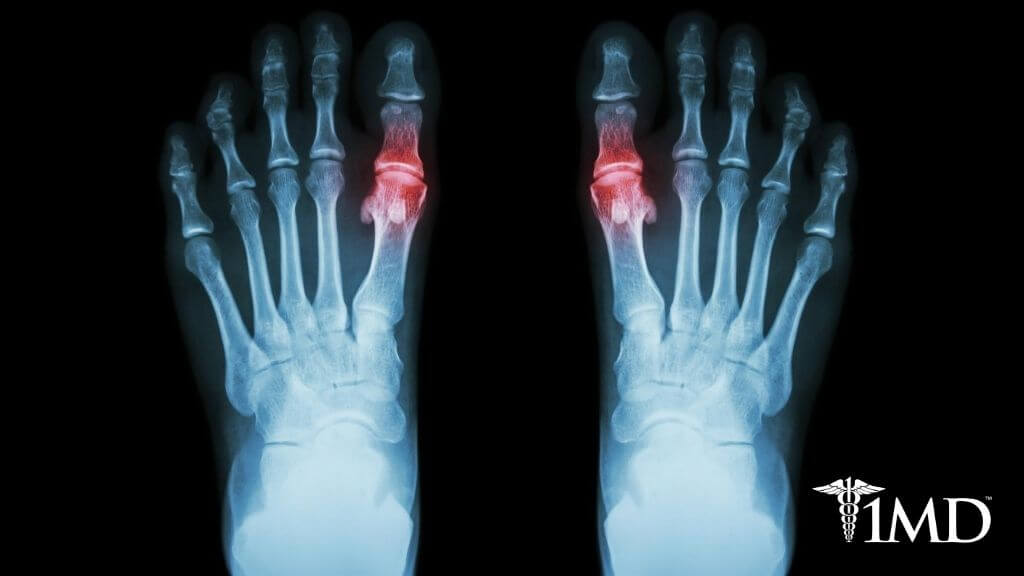

Gout can occur with osteoarthritis, rheumatoid arthritis, and psoriatic arthritis. Gout causes uric acid crystal deposits in an already inflamed and painful joint. You end up with severe pain, swelling, and tenderness.

Gout is actually a type of arthritis except with inflammation coming uric acid crystal deposits. These sharp crystals irritate the delicate joint tissues, causing more inflammation. It is the presence of these crystals that makes gout unique, and why different treatment options are required.